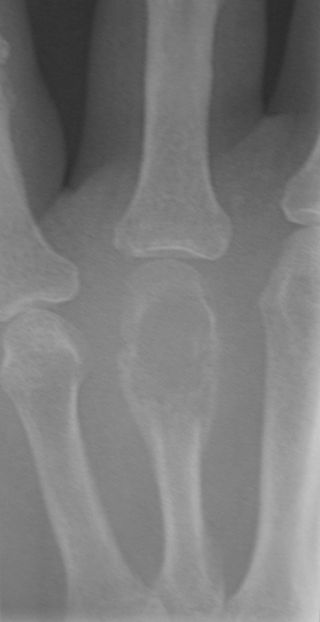

Giant Cell Tumor of the Bone

Giant cell tumor of the bone is composed of multinucleated giant cells and stromal cells that occur in young adults.

Giant cell tumor of the bone typically arises in the epiphysis of long bones, usually the distal femur or proximal tibia.

Radiology of giant cell tumor of the bone classically shows a “soap-bubble” appearance on x-ray.

Giant cell tumors of the bone are locally aggressive, and they may recur after surgical removal.